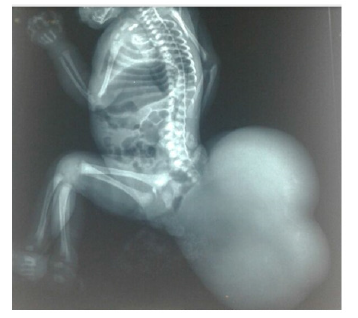

This is a female newborn born to a non-inbred parent from a well-attended pregnancy (7 ultrasounds) conducted at 34 SA and a high birth rate with a birth weight of 3kg 500, admitted to our department on the five day of life for taking charge of a mass of the gluteus region. In addition, the family reported no significant history of disease. The admission examination found a hemodynamic and respiratory stable newborn; with an irregular surface polylobed cystic mass in the buttock area with a repressed anal orifice forward (Figure 1). The rest of the clinical examination was without particularity. As part of the etiological investigation a series of additional examinations was carried out:

Standard radiography: shows the presence of voluminous opacity in the sacrococcygian region, fluid tone, or absence of calcifications (Figure 2).